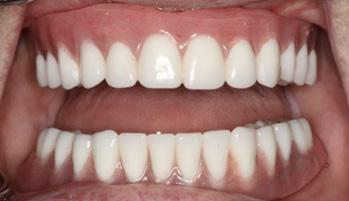

After three months of healing, the patient returned to the AEGD clinic to confirm osseointegration of implants and to begin the overdenture fabrication process. At the final impression appointment, signs of arthritis including knuckle enlargement were noted. Due to this finding, it was determined that changing the patient's final prosthesis from a Conus overdenture to a conventional overdenture was in the best interest of the patient, as the Conus would be too cumbersome for her. As seen in Figures 1 and 2, the outcome turned out very well and the patient was pleased with results and esthetics.

FIGURE 1

FIGURE 2